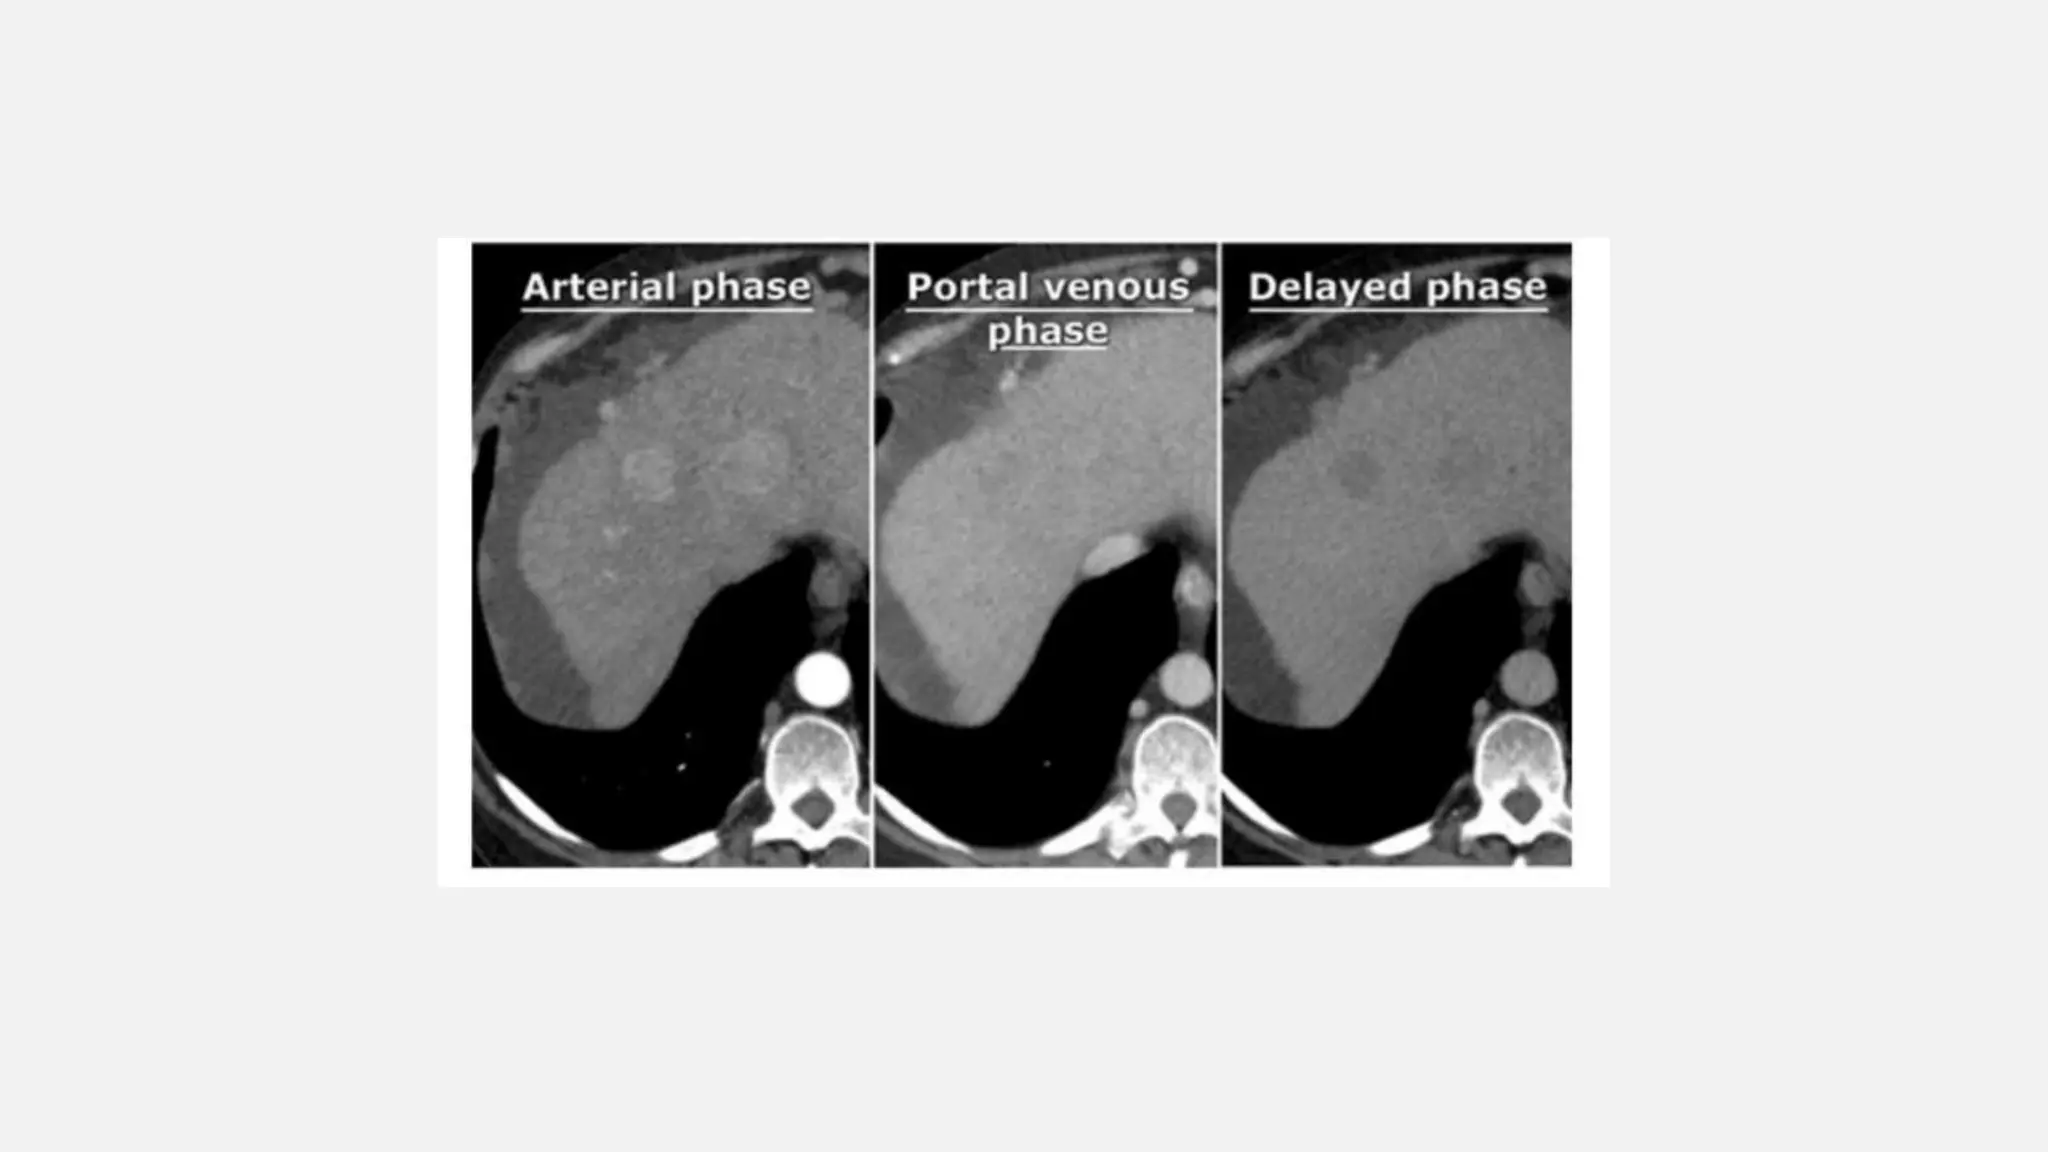

• CT TRIPLEPHASELIVER

• Mainly performed in cases of surveillance or follow up for hepatocellular carcinoma in patients with chronic liver

disease /cirrhosis and follow up after chemoembolization of liver malignancy or who had a liver transplant

• Includes arterial

• Portal venous

• Equilibrium phases.

CT PROTOCOLS • CTTRIPLEPHASELIVER • Mainly performed in cases of surveillance or follow up for hepatocellular carcinoma in patients with chronic liver disease /cirrhosis and follow up after chemoembolization of liver malignancy or who had a liver transplant • Includes arterial • Portal venous • Equilibrium phases.

• #38 In the late arterial phase at 35 sec hypervascular lesions like HCC, FNH, adenoma and hemangioma wil enhance optimally, while the normal parenchyma shows only minimal enhancement. Hypovascular lesions like metastases, cysts and abscesses will not enhance and are best seen in the hepatic phase at 70 sec p.i. Fibrotic lesions like cholangiocarcinoma and fibrotic metastases hold the contrast much longer than normal parenchyma. They are best seen in the delayed phase at 600 sec p.i. This late enhancement is comparable to what is seen in cardiac infarcts in MRI of the heart.

• #39 Liver cirrhosis with ascites. Two hypervascular enhancing liver lesions in the arterial phase. Both lesions reveal washout in the portal venous & equilibrium/delayed phases (= hypodense as compared to other liver parenchyma), consistent with HCC.